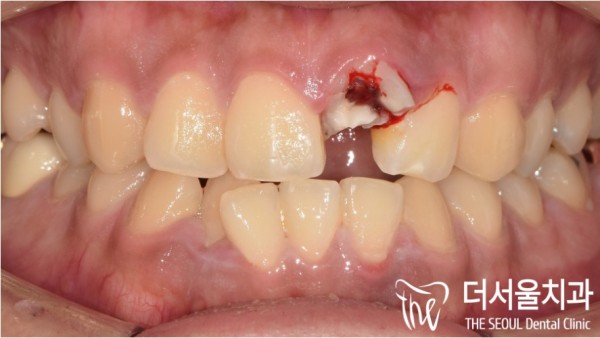

이 환자분은 평소 앞니가 앞으로 튀어나와있는 돌출입, 토끼같은

앞니를 가지고 계셨던 환자분이셨는데요.

그런데 넘어지시면서 사고로 인해 앞니가 파절되었습니다.

실제로 돌출입의 경우에 충격, 사고에 의해 앞니 외상이 발생되는

경우가 생각보다 많습니다.

However, when I fell, my front teeth were broken due to an accident.

In fact, in the case of a protruding entrance, front tooth trauma is caused by shock and accident

There are more cases than I thought.